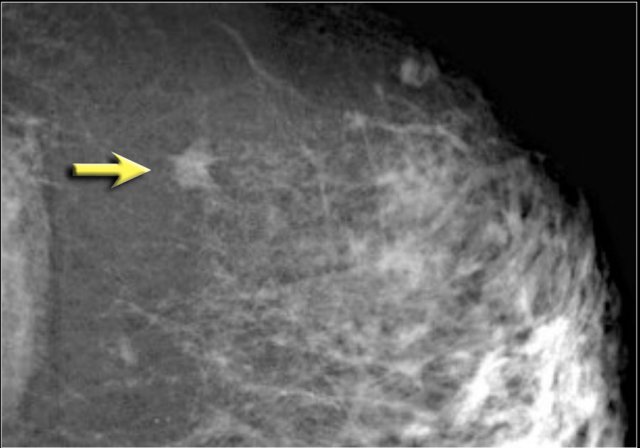

Notice the distortion of the normal breast architecture on oblique view (yellow circle) and magnification view.

A resection was performed and only scar tissue was found in the specimen.